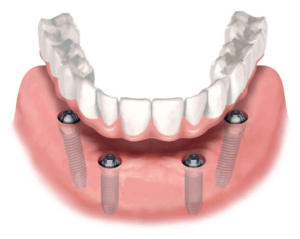

Протезирование на имплантах

Подготовительная работа включает все необходимые процедуры. После этого, при двухэтапном протоколе, ждут, пока импланты приживутся, затем делают слепки и изготавливают зубные протезы по общей схеме.

При одноэтапном протоколе, установка временных конструкций предусмотрена сразу после имплантации. Примерно через год изготавливают и устанавливают постоянные протезы. Цены на протезирование на имплантах могут быть выше, но конструкции служат дольше и более надежны, что делает стоимость не такой высокой, как кажется на первый взгляд.

- Установка имплантатов при несъемном зубном протезировании и с целью создания опоры для съемных конструкций протеза;

Имплантация зубов. Установка импланта возможна по двухэтапному и одноэтапному протоколу. Во втором случае врач удаляет зубную единицу и сразу устанавливает имплант.

Подготовка к протезированию на имплантах

Перед имплантацией зубов операцией пациенту необходимы:

3D-моделирование. Все данные переносятся в программу. Врач разрабатывает детальный макет челюстной системы, определяет количество имплантов и места вживления. Подбирает материал будущего протеза.

Панорамный снимок, КТ. Позволяют увидеть состояние челюстной системы, костной ткани, нервов, носовых пазух. На основании этого врач расписывает план лечения.

Фотометрия и кондилография (при частичной или полной адентии). У пациента берут фотопараметры с открытым, закрытым ртом, с улыбкой, без нее. Это необходимо для создания индивидуального протеза. Кондилография предоставляет данные о работе височно-челюстного сустава.

Анализы крови, мочи (не всегда). Необходимы для оценки вашего состояния здоровья, свертываемости крови, а также для выявления острых инфекций.

Санация полости рта. Перед установкой имплантов ротовая полость должна быть стерильной: лечится кариес, периодонтит. Купируется воспалительный очаг. Если зубы здоровы, обязательно проводится профгигиена рта.

Костная пластика (не всегда). Операция подразумевает наращивание кости в месте вживления зубных имплантатов для их полноценной работы. Проводится, если у пациента вследствие длительного отсутствия единиц сильно атрофировалась костная ткань.

Снятие слепков для временного протеза. После вживления имплантов устанавливают временную ортопедическую конструкцию. Она обеспечивает жевательную и защитную функции, сохраняет полноту зубного ряда, эстетику улыбки вплоть до установки постоянного протеза.

Например, несъемный покрывной протез для имплантации по технологии All-on-4, заменяет полную съемную конструкцию. Главное преимущество — надежное прикрепление к челюсти. Человек может полноценно жевать и разговаривать без стеснения.